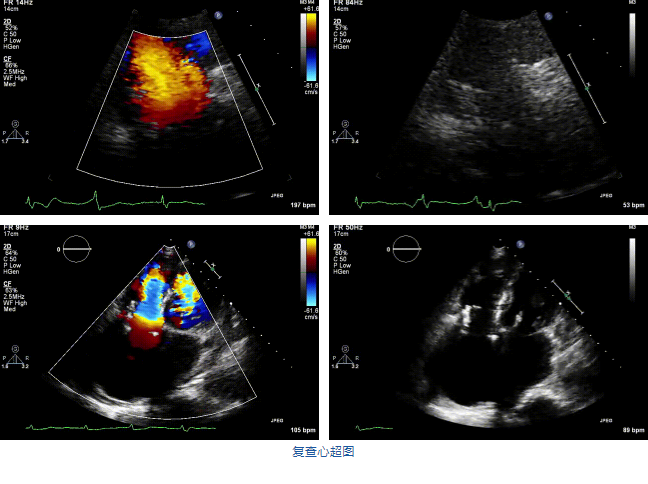

兩例患者是都是外科手術高危的極重度三尖瓣反流的老年女性,反復下肢水腫、腹脹、納差,活動耐力減退。一例患者風濕性心臟病,二尖瓣生物瓣置換術后,房顫,心超顯示三尖瓣極重度反流(最大反流寬度15mm);另一例患者房顫,心超示三尖瓣極重度反流(最大反流寬度23mm)。

結合術前CT評估結果,葛均波院士團隊最終決定選用LuX-Valve Plus 50mm和55mm兩種型號的瓣膜,并于2021年11月30日順利完成LuX-Valve Plus經(jīng)血管三尖瓣置換術,手術室即刻拔除氣管插管,術后第二天轉(zhuǎn)出心內(nèi)科監(jiān)護室,下床活動。術后患者三尖瓣反流癥狀得到顯著改善,復查心超結果顯示人工三尖瓣瓣膜支架固定穩(wěn)定,瓣葉關閉形態(tài)未見異常,未見明顯反流。